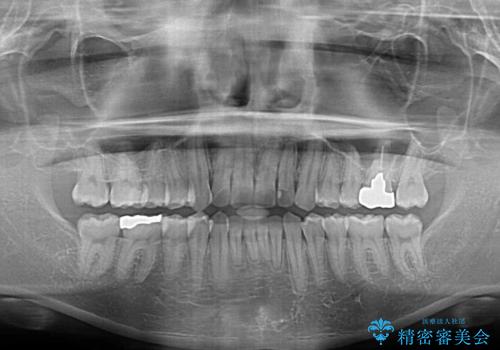

- 上下前歯のデコボコを気にして来院された患者様です。

マウスピース矯正でもワイヤー矯正でも対応可能でしたが、インビザラインによる自己管理が煩わしいとのことで、ワイヤー装置にて矯正治療を行うこととしました。

口元はやや突出感がありましたが抜歯矯正をするほどではないため、舌突出癖を改善するトレーニングをしっかりと行っていただき、現在よりも唇が閉じやすい位置に仕上げていくこととしました。

下顎前歯が思っていた以上に動きが悪く、想定よりも期間がかかってしまいました。

矯正治療後には気になっていた銀歯をセラミックで自然な色に仕上げました。